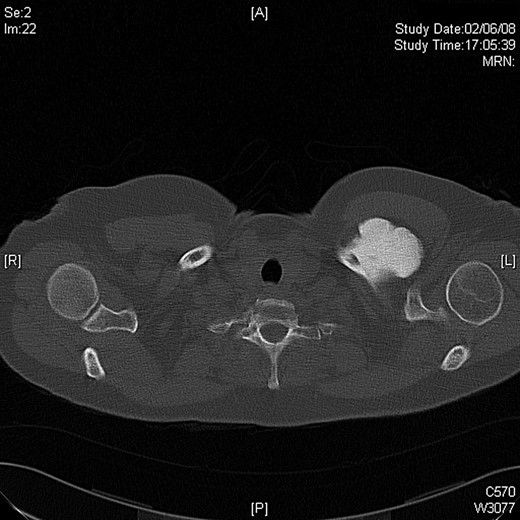

A 45-year-old woman presented with a 20-year history of a lump in the mid-third of the left clavicle, which had recently increased in size to 10 cm in diameter. Plain X-ray, computed tomography (CT) chest and clavicle, and bone scans were used to image the lesion (Figs 1–3). Radiology reported the lesion as a parosteal osteosarcoma, based on the CT appearance of tumour growing into the medulla of the mid-third of the clavicle; not usually a feature of an osteochondroma or an osteoma. Biopsies showed dense sclerotic bone, with no obvious malignant features. To confirm diagnosis complete excision of the tumour was needed, with a partial excision and scraping the lump off the surface deemed unsafe. The patient was informed that, following a total claviculectomy, a 30% functional loss (29.5% [8]) in her left shoulder power would be expected. Her active lifestyle meant this result was unacceptable, so she opted instead for excision of the tumour plus the adjacent clavicle, irradiation and reimplantation of the bone with internal fixation, despite this being relatively experimental. If successful, she would have virtually normal function. Although possible risks included infection or development of non-union, which would require further surgery or possible complete claviculectomy, it was deemed oncologically safe with a low risk of complications.

Preoperative CT scan, axial view showing the extent of the tumour.